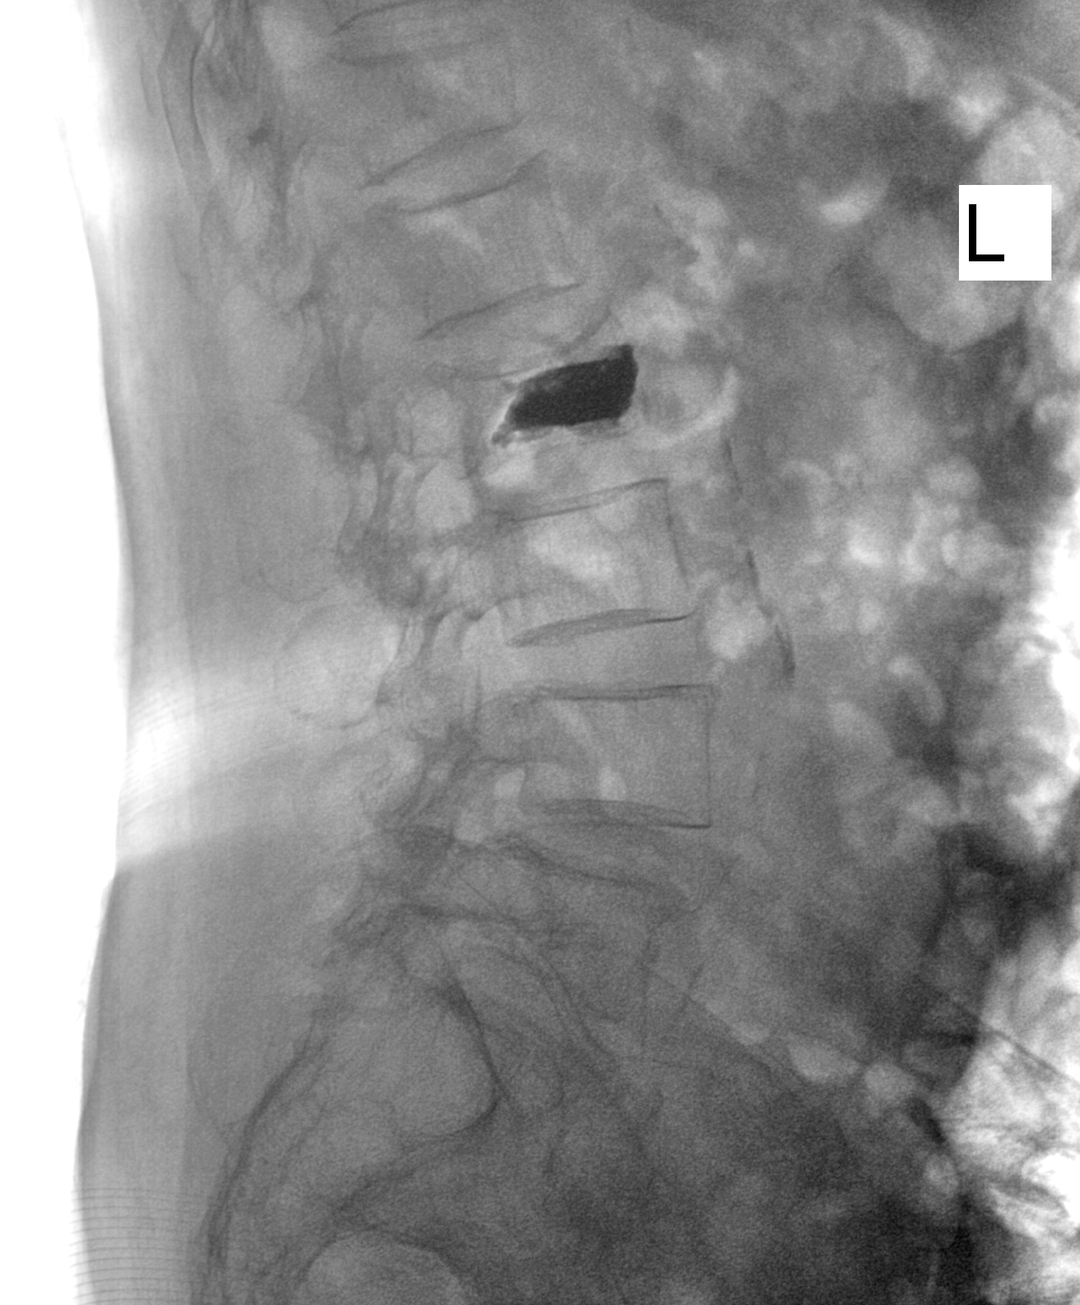

疗效立竿见影。术后,李奶奶的腰痛得到了根本性缓解。第二天,她便在医护人员指导和家人搀扶下,尝试下床并缓慢行走,生活质量显著提升。术后影像复查显示,骨折椎体复位良好,内固定位置精准。

术后X光片显示,骨折椎体高度恢复,内置支架位置良好。